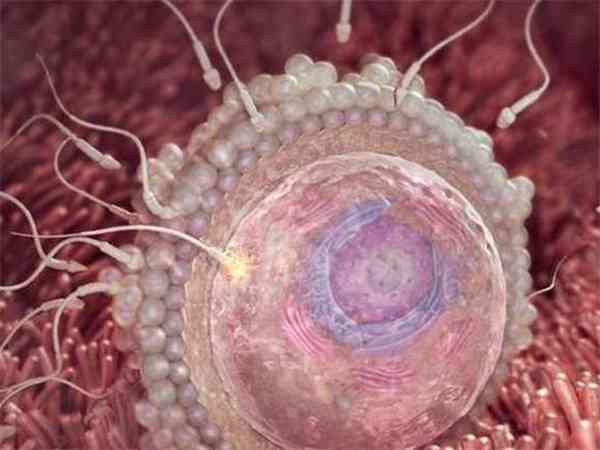

当患者的amh值为0.41的时候,做试管的成功率是并不高的,但是如果患者取到的卵子质量比较好,那么会对试管成功率有正面的影响的。因为患者在试管促排卵过程中得到的卵子质量比较好的话,会对患者做试管婴儿的成功率有一定影响的,会使试管的成功率有所提高,除了卵子数量以外,卵子质量也同样是影响试管婴儿成功率的关键因素之一。

性激素六项检查amh0.41储备功能差做试管婴儿的成功率并不高,但毕竟每个患者的身体情况不同,其成功率也是因人而异的。amh也称“抗缪勒管激素”,正常情况下女性的amh值应该在2-6.8ng/ml之间,当amh值低于正常数值时,则表示女性卵巢已经衰竭,卵泡储备少。但试管婴儿的成功率与卵泡的数量是没有关系的,理论上只要有一颗卵子,只要卵子质量好,就有可能成功。因此,amh0.41对试管婴儿成功率的影响不大,卵子质量好坏是影响试管婴儿成功率的关键因素。

AMH值越低则卵巢功能越差,当AMH值低于0.7ng/ml时,表示卵子库存量已严重不足,自然受孕的几率非常低。但如果卵子质量优质的话,试管婴儿成功率还是比较高的,因为卵子质量是决定试管婴儿成功率的关键因素。下面就说说amh只有0.41做试管如何进行挽救治疗,具体如下:

- 3. amh值0.41,只要amh值没有为“0”,那么就有卵泡存在的机会,做试管婴儿,理论上只要一颗卵子,就代表了一个新生命,抢救好每一颗卵子,这是试管治疗的基本原则,关键是个人的争取意愿。